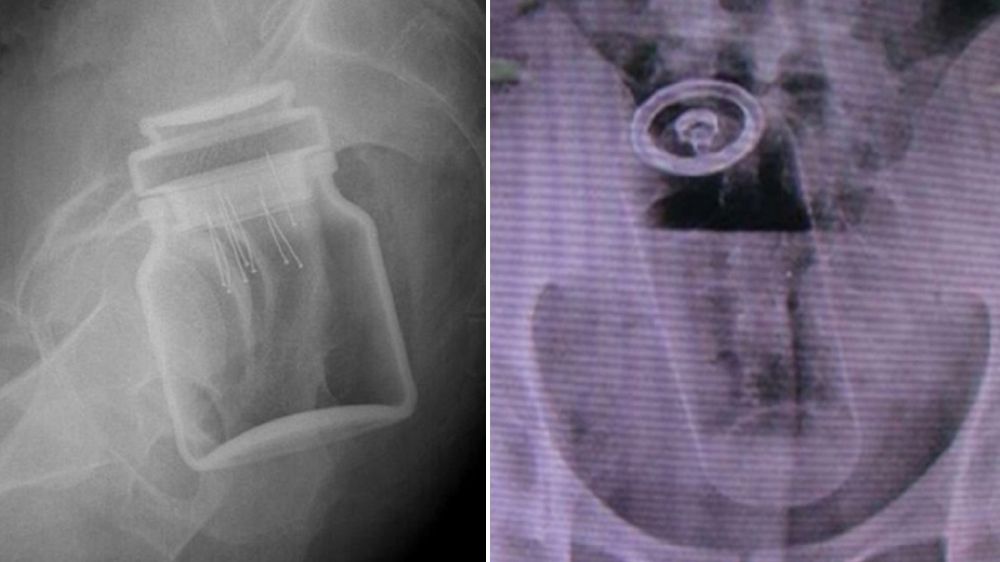

/ 8Słoik z kawą

Podobno pacjent był tak zawstydzony, że nawet nie próbował się tłumaczyć.